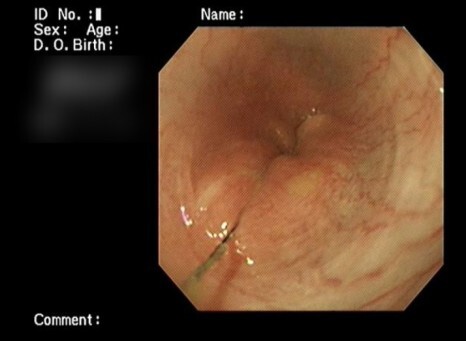

내시경으로는 제거가 불가능한 상태이기 때문에

개복수술을 통한 제거를 진행하기로 하였습니다.

선이물을 먹으면 장 연동운동으로 인해 선을

가운데 두고 장이 아코디언처럼 겹쳐지는 현상이

나타납니다.

다행히 괴사가 의심되는 부분은 없어서

절제/문합 수술은 진행하지 않았습니다.

대신 두 곳을 절개하여 이물을 제거하는

수술을 진행하였습니다.